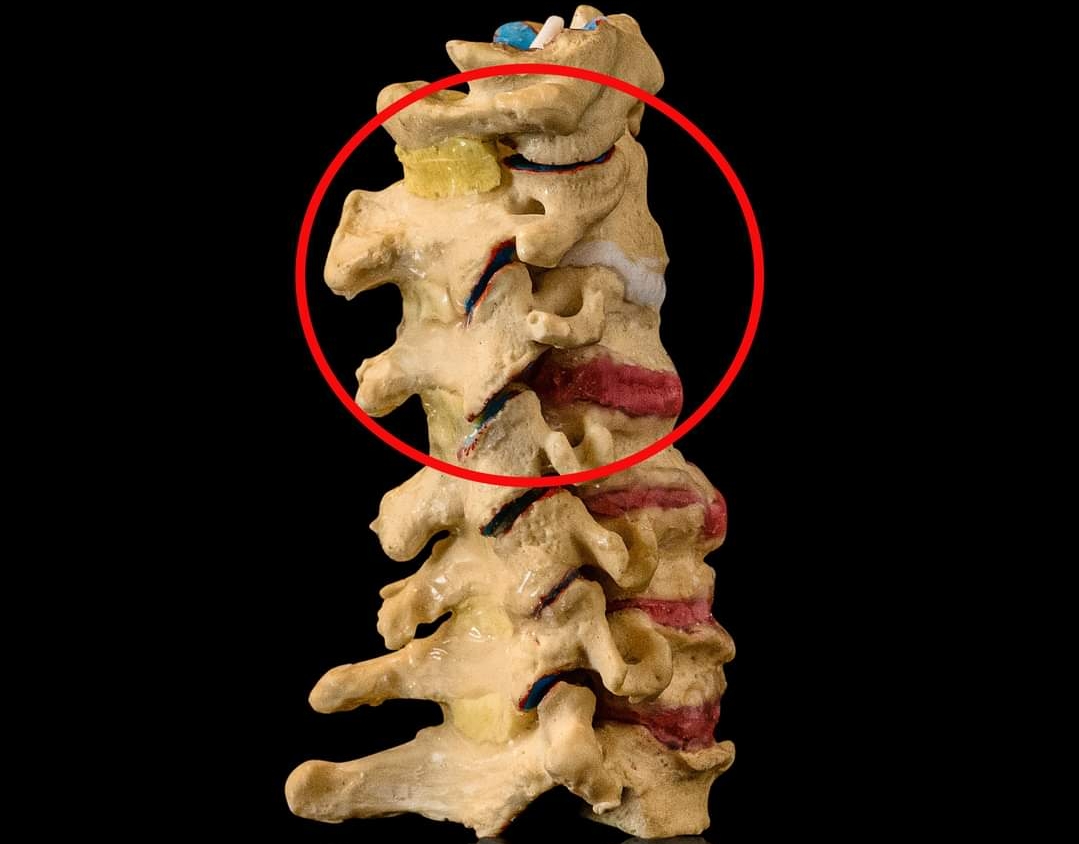

The majority of symptomatic disc herniations are found at the lower two lumbar interspaces, that is, about 50% at L4–5 and 47% at L5-S1 (1). The remaining 3% are found at higher lumbar levels (1). A r...